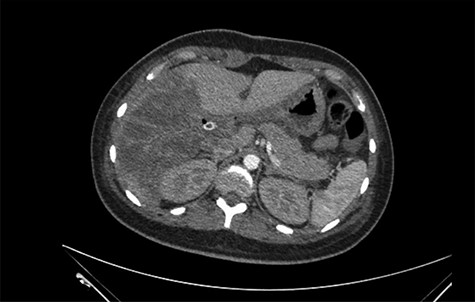

She was referred to our center on postoperative Day 4 due to progressive jaundice and encephalopathy. A triphasic contrast-enhanced abdominal computed tomography (CT) was done revealing a right liver lobe infarct, absence of the right and left hepatic arteries (Fig. 1), presence of an accessory left hepatic artery from the left gastric artery (Fig. 2) and right portal vein thrombosis with extension to the main portal vein (Fig. 3).

Accessory left hepatic artery (white arrow) on the arterial phase of the triphasic contrast-enhanced abdominal CT.